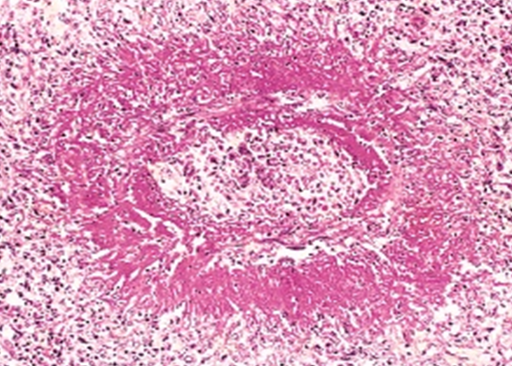

Describe what is circled in this image

Artery occluded by thrombus in lung

Thrombi adherred to wall of vessel

Endothelial damage, layer of platelet anchor clot